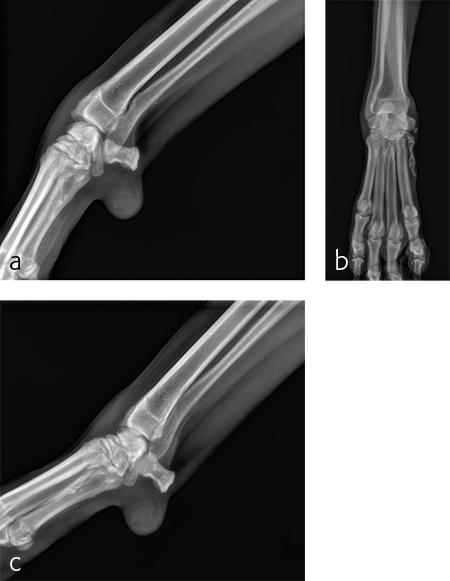

The patient was anesthetized and placed in ventral recumbency. Arthroscopic evaluation of the right antebrachiocarpal joint revealed synovitis and partial tearing of the palmar radiocarpal and ulnocarpal ligaments (Fig 4). A decision was made to perform a pancarpal arthrodesis due to arthroscopic evidence of damage at this level of the joint. A dorsal approach was made to the right carpus. The articular cartilage was debrided at all levels of the carpus. An autogenous cancellous bone graft was harvested form the right proximal humerus and was applied at the arthrodesis site.